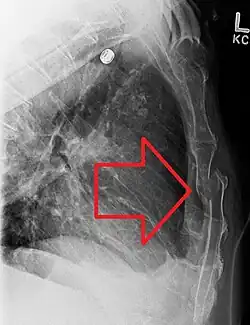

| A displaced sternal fracture as seen on plain X-ray | |

X-rays of the chest are taken in people with chest trauma and symptoms of sternal fractures, and these may be followed by CT scanning.[13] Since X-rays taken from the front may miss the injury, they are taken from the side as well.[14]